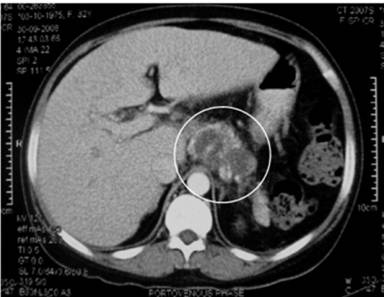

The most commonly affected part of the pancreas was the body region (100%; Figure 1), followed by the head (75%; Figure 2) and tail (50%; Figure 3). The involvement was typically multi-focal (75%; Figures 1 and 2) and in the form of micro-abscesses. Only one patient (25%) had a large focal solitary abscess (Figure 1), affecting the body of the pancreas. Other associated pancreatic findings included splenic vein thrombosis (Figure 2), peripancreatic inflammations and peri-pancreatic fat streaking. Extra-pancreatic manifestations included blood (4 patients), liver abscesses (3 patients; multiple micro-abscesses (Figures 3 and 4) or large ‘honeycomb’-like abscesses), ascites (2 patients; Figures 3 and 4), splenic abscesses (2 patients; Figures 2 and 4) (which also has the ‘honeycomb’ appearance), psoas abscesses (2 patients) and lung (1 patient).

Figure 1. Axial tomography image showing a large multi-loculated pancreatic abscess (circle) affecting the body of the pancreas (Case #1). |